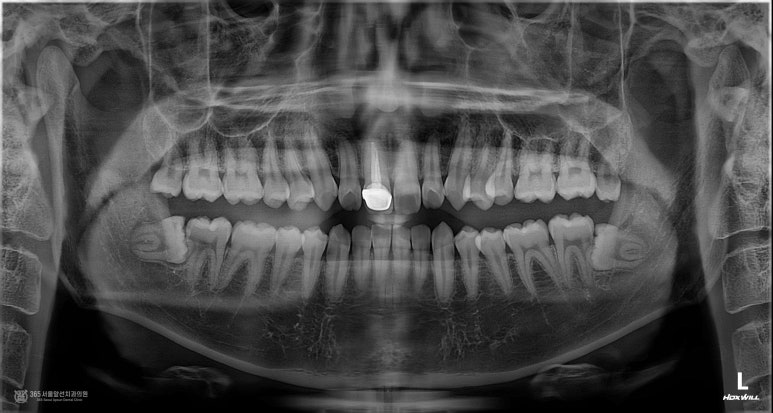

촬영일시 : 2024.09.13 주안동치과추천 365서울앞선치과의원 초진 내원 당시 파노라마 엑스레이 사진인데요. 사진상 오른쪽 중절치에 신경치료가 되어 있고 크라운이 씌워져있는 것이 관찰됩니다.

촬영일시 : 2024.09.13 고름이 상당히 커보입니다. 즉, 오랫동안 염증이 지속되어 치아 뿌리 끝에 커다란 고름주머니를 형성시킨 것으로 유추되는데요.